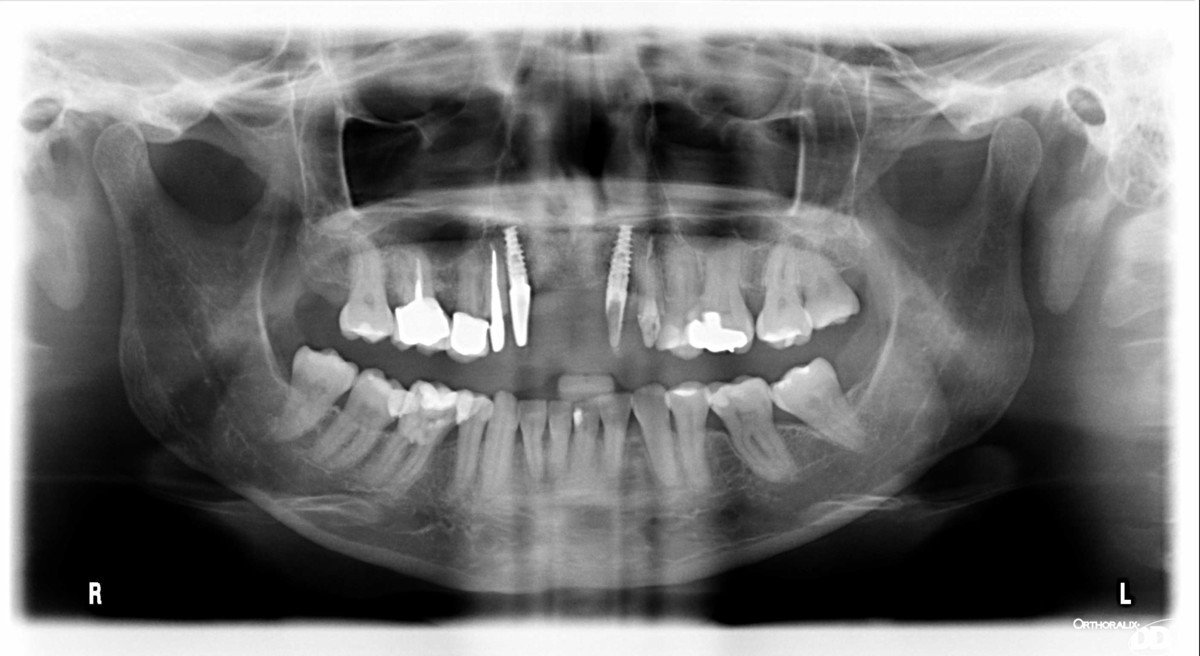

Implantes en 41, 46 y 47

Implantes en pieza 41, 46 y 47, dos son de hexágono externo y uno de conexión interna. Todos ellos el tornillo interior es de métrica 2. Deben de tener al [...]

Acude el paciente con prótesis realizadas tipo all on4 de la clínica I-DENTAL. Tenemos que realizar las prótesis nuevas por fractura, necesitamos saber qué implantes son y la marca para [...]